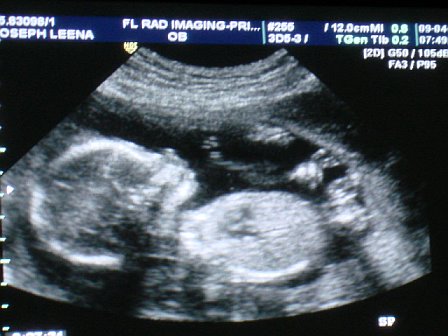

jessbaby

My boys!

Member since 1/06 5292 total posts

Name: Jessica

|

Re: Sono pics... can i see your 20 week ones?

Here is mine. I love it!

Posted by jessbaby

IMAGE

See that's what i'm talking about! That's a good one compared to mine!